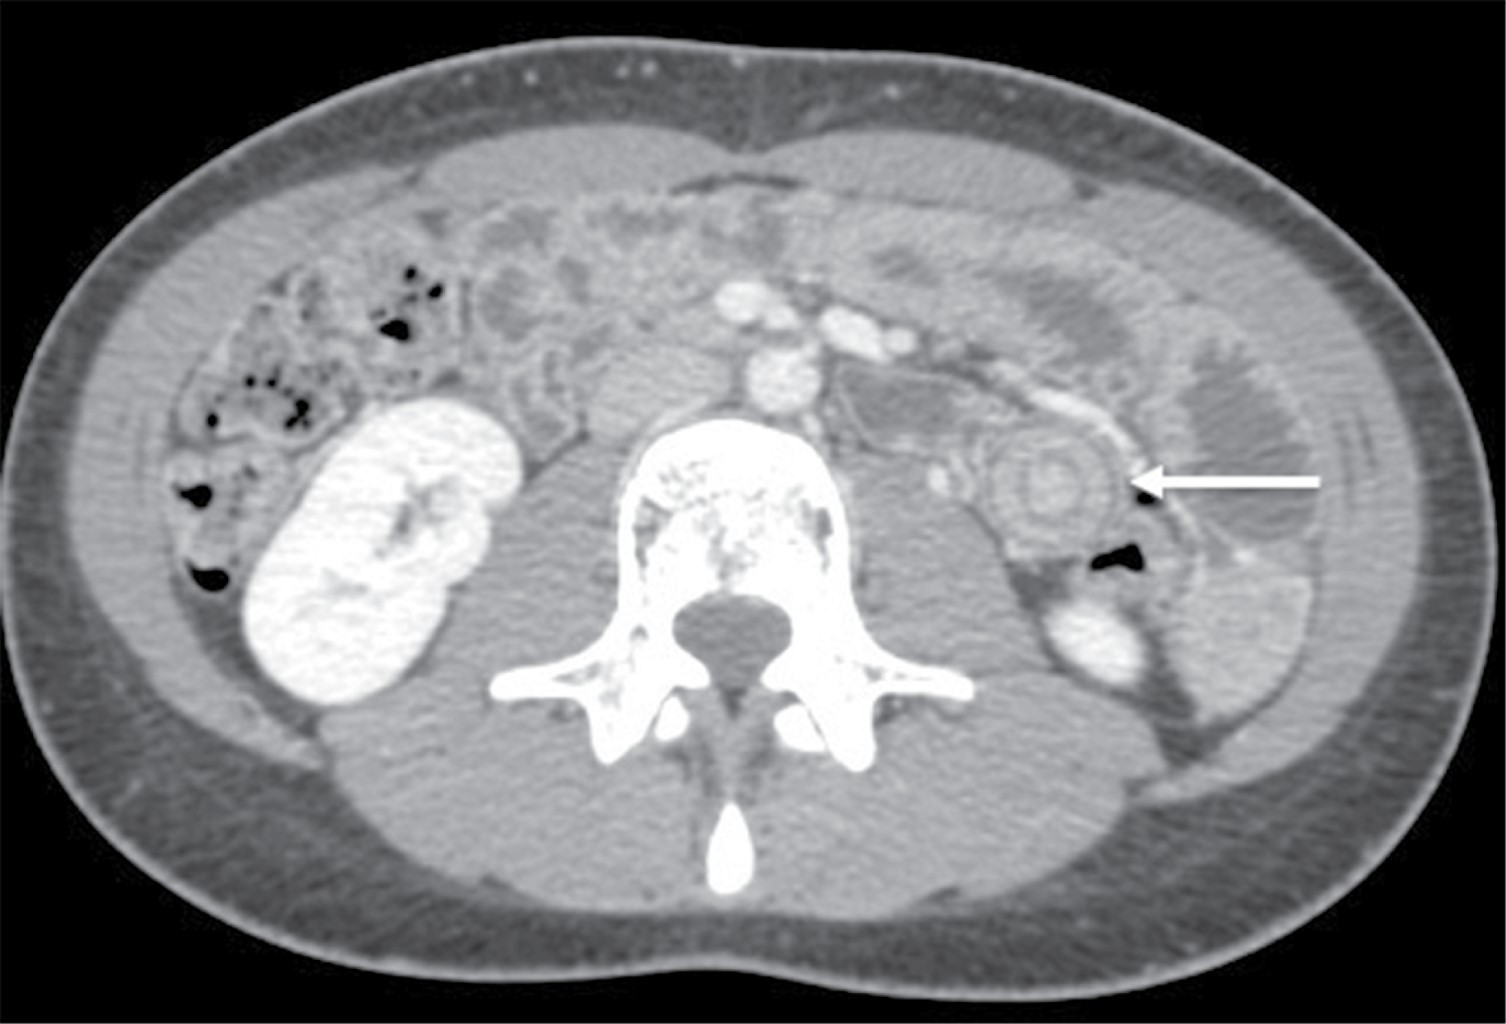

Ante la duda diagnóstica, se solicitó una tomografía con contraste intravenoso. Se reportó poca cantidad de líquido libre intraabdominal y discreto engrosamiento generalizado de las paredes intestinales sin datos de obstrucción o perforación de tubo digestivo. En el corte axial, a nivel del flanco izquierdo y en la topografía del yeyuno, se observó una imagen en "signo de diana" o "tiro al blanco" (Figura 1) misma que, en las imágenes de reconstrucción sagital y coronal, corroboró un deslizamiento de 2.3 cm de intestino invaginado dentro de sí mismo (Figura 2A y B), dando como resultado un diagnóstico compatible con intususcepción yeyuno-yeyunal.5

Figura 2